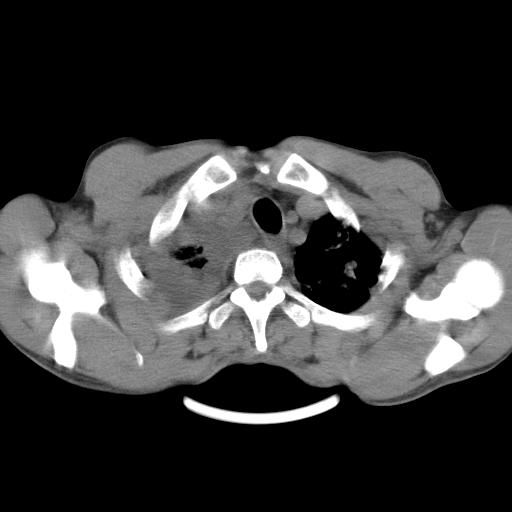

男性,44岁,结核病史多年。现胸闷气短,咳嗽,偶咳血。

右侧胸腔积液

右肺下叶不张

双肺多发结节影最分空洞形成考虑占位不除外结核

双肺陈旧性病变

1、右侧大量胸腔积液伴右肺压缩性膨胀不全,建议抽液治疗后复查 2、两肺继发性tb伴空洞形成。

1)两肺继发性肺结核伴空洞形成,左肺多发性结核球。2)右侧大量胸腔积液伴右肺部分膨胀不全。3)纵隔淋巴结肿大。